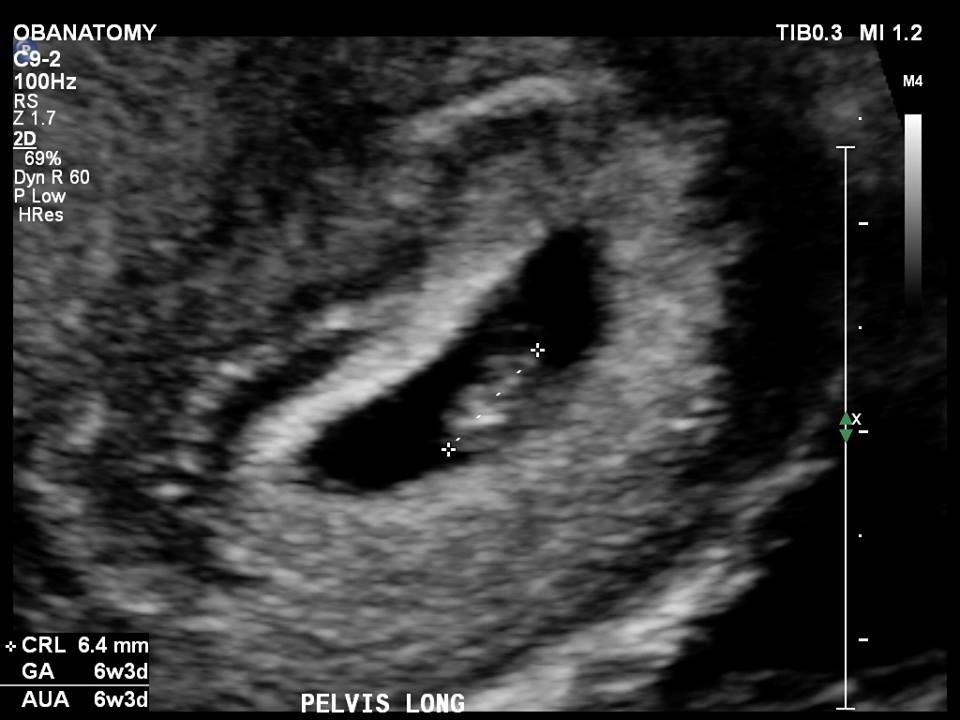

• My little munchkin at 6 weeks and 3 days, it was so small, and so adorable, and I got to hear it's heart beat :)